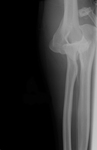

Anteroposterior x-ray view of an elbow dislocation

Personal collection of Dr Paul Novakovich